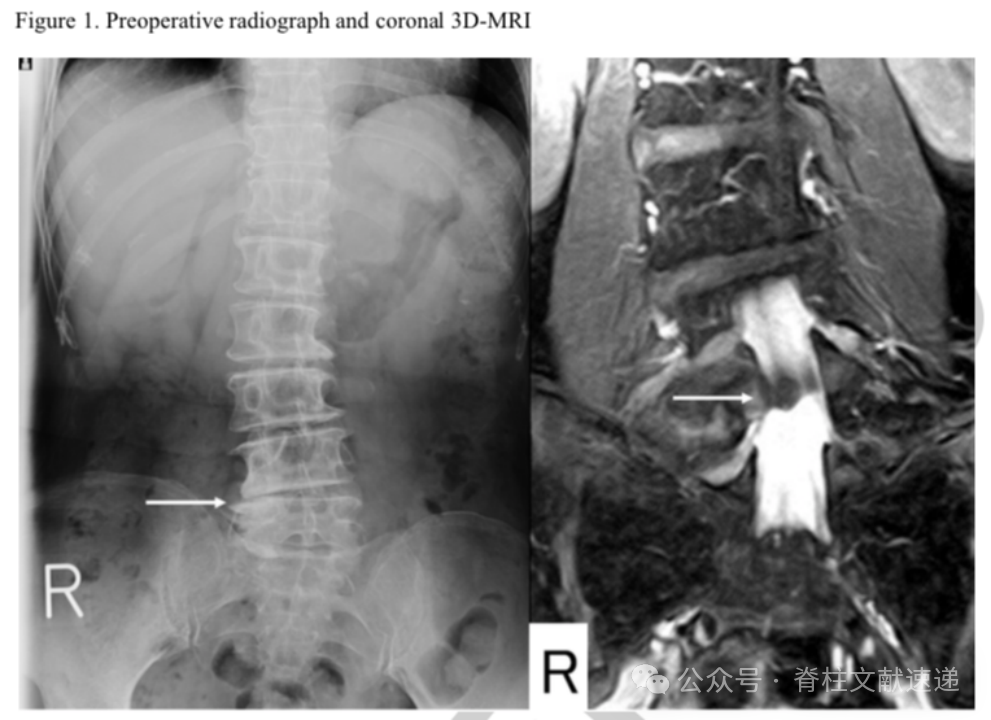

文中病例:69岁女性,右下肢放射性疼痛。存在脊柱侧弯,髓核摘除术后2月进行了融合手术。